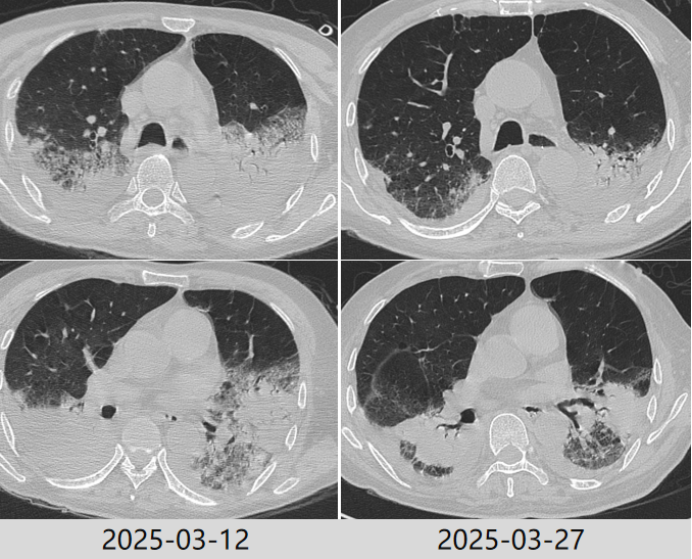

根据病原学结果,先后予以米卡芬净+美罗培南、哌拉西林他唑巴坦+环丙沙星头孢他啶阿维巴坦抗感染治疗2025324日拔管3月27日复查胸部CT提示肺部病变好转吸收(图5)。患者仍有明显咳痰困难,乏力,四肢肌力下降,经康复锻炼恢复欠佳

5  复查胸部CT对比

2025年4月16日复查胸部CT明显进展(图7)。调整头孢哌酮舒巴坦为美罗培南+莫西沙星抗感染,无创呼吸机辅助通气,入重症康复科ICU。

7  患者胸部CT较前变化